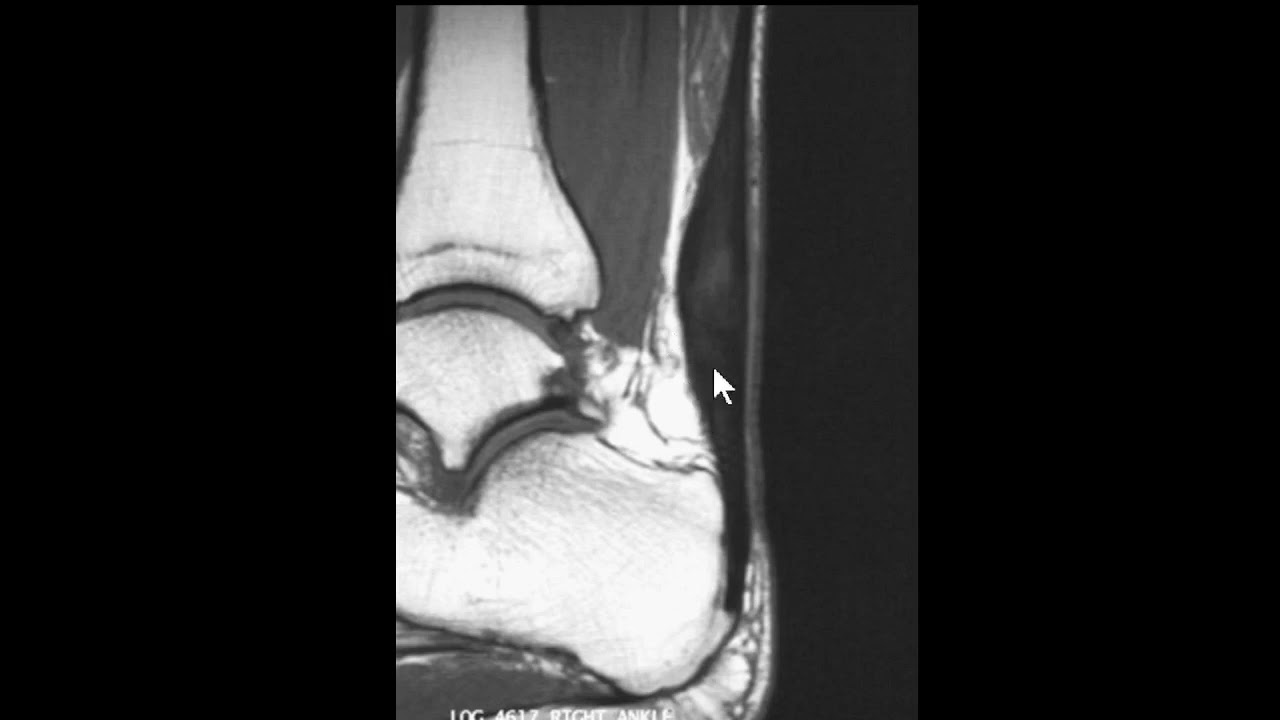

saudações vamos aqui a Mais Um Caso o contexto clínico é de um paciente que sofreu uma torção aguda do tornozelo e temos essa ressonância magnética aqui um axial DP com saturação de gordura e vamos observar aqui aqui é a fíbula corte aqui no plano axial aqui a fíbula aqui o talos aqui a tíbia né então o ligamento tíbio talar anter inferior está íntegro vamos descendo aqui aqui é a topografia do ligamento talofibular anterior aqui o ligamento talofibular posterior e você observa aqui no ligamento talo fibular anterior veja que ele está espessado está com hipersinal e

você nota nitidamente uma solução de continuidade né uma ruptura aí do ligamento talofibular anterior e edema ao seu redor existem outras alterações mas a gente vai se ater a essa alteração o ligamento talofibular posterior ele tem esse aspecto radiado né rajado é normal e o ligamento calcâneo fibular esse aqui na ponta da seta está íntegro apesar de haver edema ao redor dele então o ligamento talo fibular anterior rompeu e essa é a rotura mais frequente ligamentar no tornozelo do ligamento talofibular anterior aqui pra gente ver um comparativo com um tornozelo normal você Observe aqui a